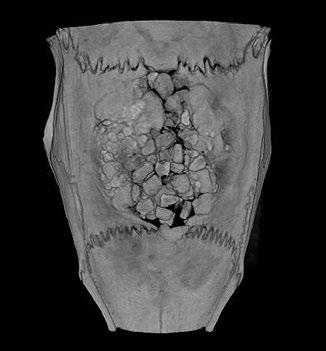

Researchers at City University of Hong Kong have developed a new, non-invasive imaging approach to examine the remains of beached marine mammals, like whales and dolphins. The approach, called virtopsy, was described in the journal Frontiers in Marine Science and can be used to determine the cause of death. It can also gather useful information about the animal before it died, such as its general health, as well as if it suffered human impacts, such as vessel collision or marine pollution.

Virtopsy uses modern imaging techniques to examine dead marine mammal remains. It is performed before conventional necropsy, the animal equivalent of human body-opening autopsies, or can even replace it in some cases.

“Virtopsy appears to be more accurate, time-saving and non-invasive compared to conventional necropsy, with less risk of

disease contraction for veterinarians and human rescuers,” says CityU radiological clinician Brian Chin-wing Kot.

In Hong Kong, marine mammal remains are often found badly decomposed on beaches, making conventional necropsies very difficult. Virtopsies provide an effective alternative to examine external and internal structures.

Kot and his team have performed virtopsies on more than 200 beached marine mammals using post-mortem computed tomography (PMCT) and post-mortem magnetic resonance imaging (PMMRI). The work shows that PMCT identifies bone lesions, foreign bodies, pathological gas formation and organ trauma better than conventional necropsy. PMMRI is

better at identifying soft tissue injury, organ trauma and non-traumatic pathology.

The team also found that PMMRI provides more information on decomposed brains than PMCT. Additionally, it should be used in conjunction with PMCT to detect soft tissue lesions and brain pathologies, as PMMRI alone is more prone to showing unwanted artefacts from gas and foreign bodies.